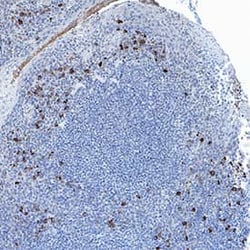

Human MFAP3 Antibody, R&D Systems™

MFAP3 Monoclonal antibody specifically detects MFAP3 in Human samples. It is validated for Immunohistochemistry

| Immunohistochemistry | |

| Immunohistochemistry 5-25 ug/mL | |